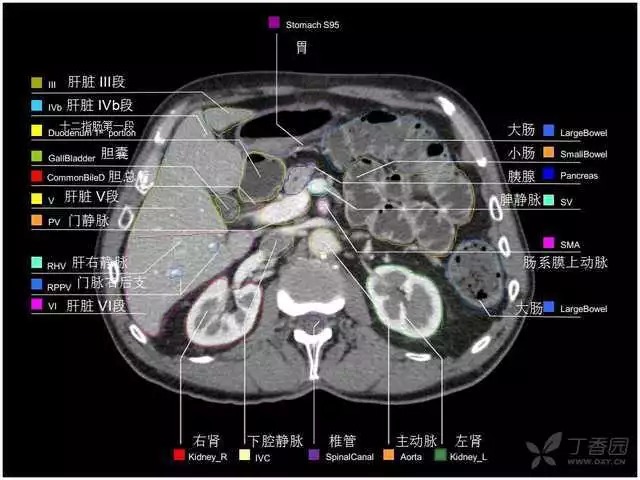

腹部肝脏高清CT断层的图谱

全腹部高清CT图谱,淋巴结彩色图谱,血管解剖图谱大汇总!

超声肝脏分叶及分段

肝脏分段和基本解剖学标志